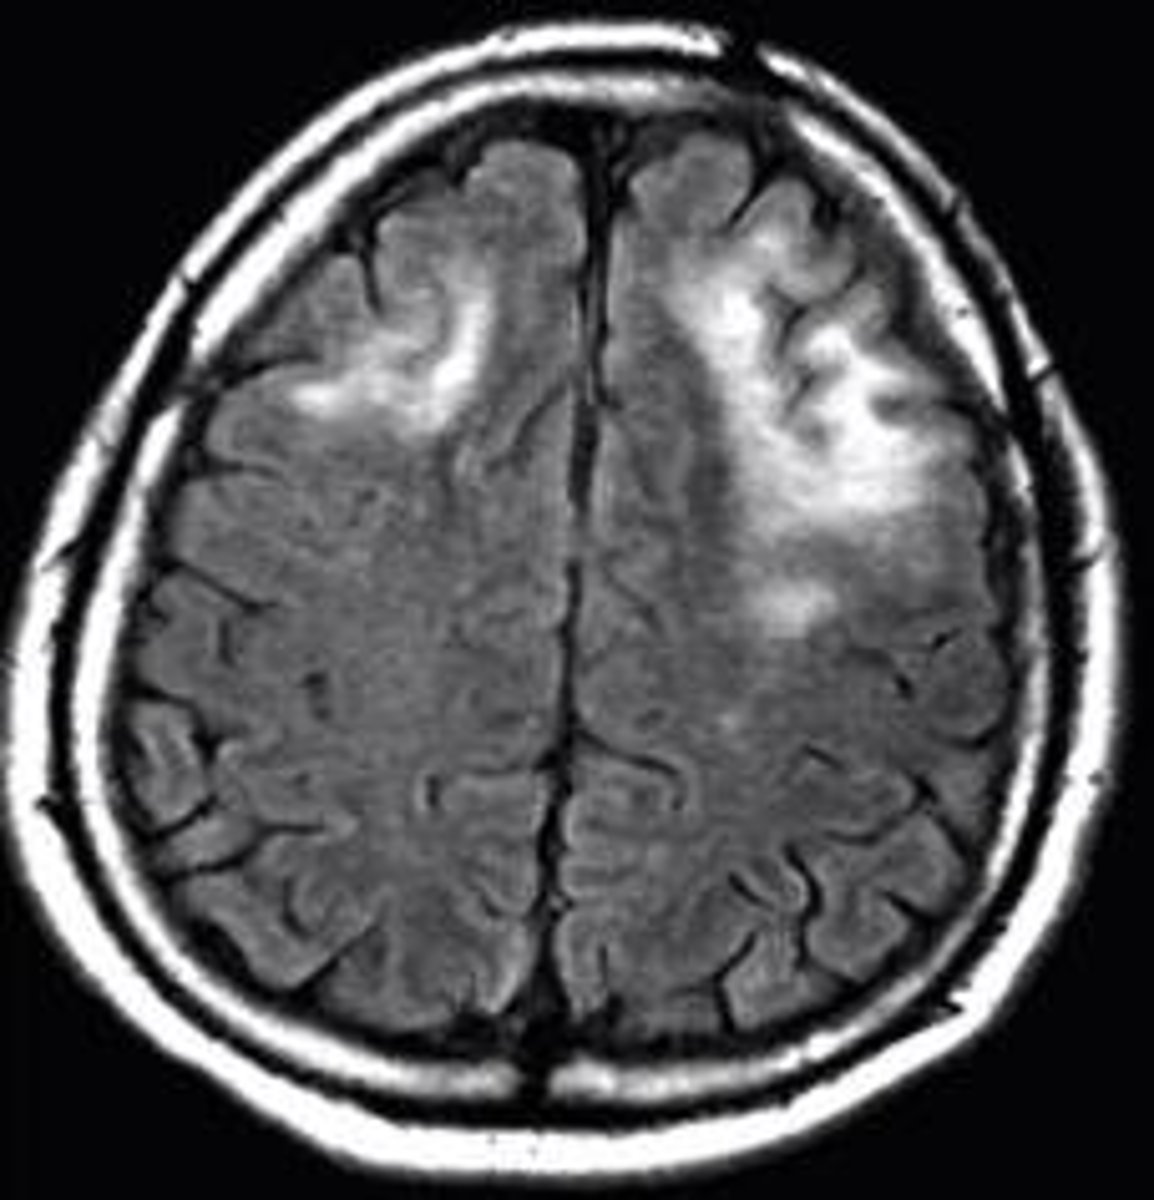

MRI shows multiple demyelinating, non-enhancing lesions with no mass effect seen in immunocompromised pt that has hemiparesis and disturbed speech.

Progressive multifocal leukoencephalopathy (PML)

- JC virus, human polyomavirus

- cortical white matter

- survival 6 mo. post dx.